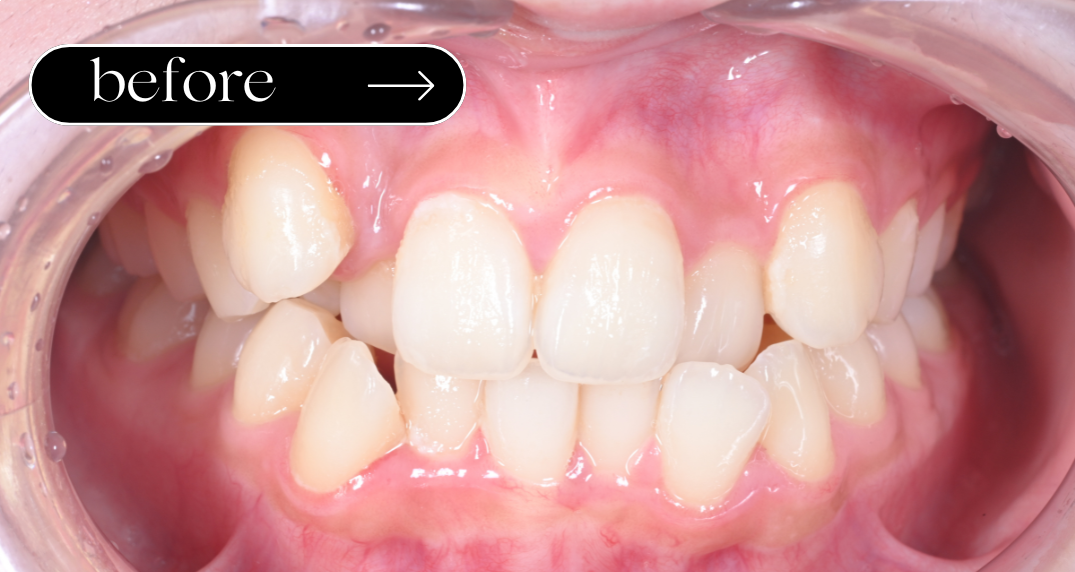

八重歯が目立つ、前歯の中心のずれが気になるとのことで来院されました。便宜抜歯を行い、矯正治療により歯並びや咬み合わせの改善を行いました。

期間:1年8ヶ月 回数:月1回受診

- 全顎矯正治療(Ⅱ期治療) 700,000(税込 770,000)

- 便宜抜歯 1歯あたり 11,000 (計)2本 22,000

矯正治療では、痛みや口内炎、歯や歯ぐきへの影響、治療期間の延長や後戻りなどが生じる可能性があります。適切な通院とセルフケアが重要です。